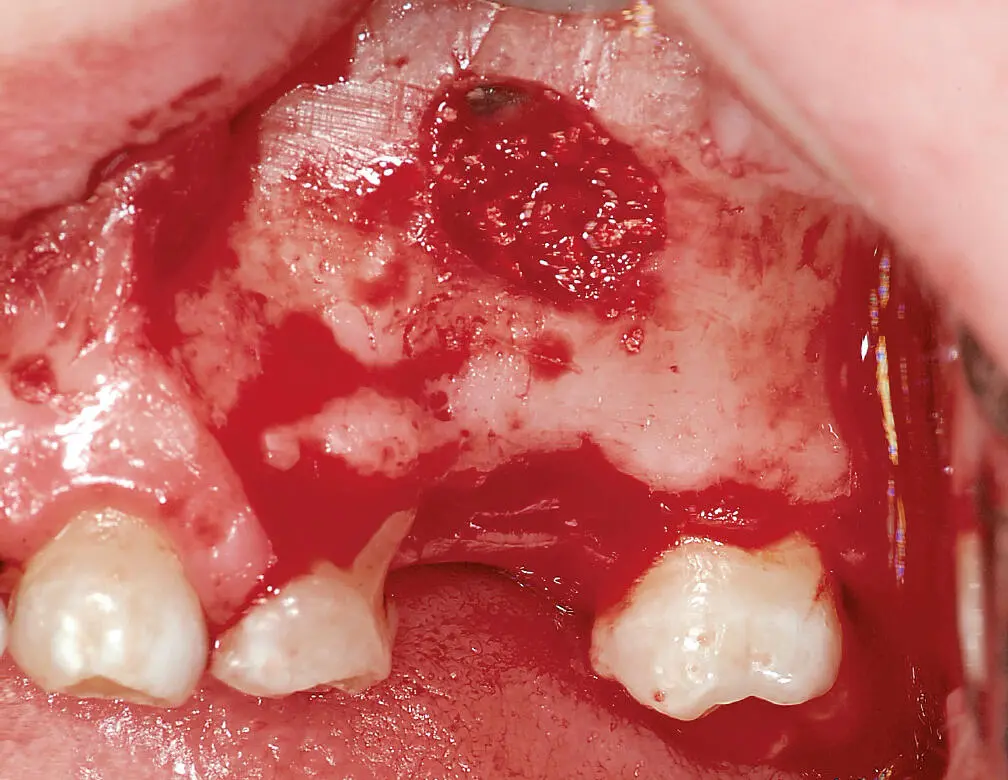

Im Rahmen der „Consensus Reports“ 2015 der European Association for Osseointegration (EAO) wurde kein ausreichender Nutzen für die präoperative Antibiotikaprophylaxe im Fall einfacher Implantationen bei gesunden Patienten gesehen. Insbesondere im Hinblick auf das Problem der Antibiotikaresistenzentwicklung und das Vorkommen von unerwünschten Nebenwirkungen wird daher die Empfehlung zur perioperativen Antibiotikaprophylaxe kritisch betrachtet. Für kompliziertere Fälle konnte hingegen ein Nutzen der Prophylaxe zumindest nicht ausgeschlossen werden 27,28( Abb. 1). Eine prolongierte Antibiose über 3 bis 5 Tage kann bei Augmentationen erwogen werden, denn es hat sich gezeigt, dass unabhängig von der Art der Knochenentnahme eine bakterielle Kontamination des Augmentationsmaterials nahezu unvermeidbar ist ( Abb. 2). Auch bei der Verwendung von Knochenersatzmaterial sollte eine prolongierte Antibiose über einige Tage verordnet werden, da es sich primär um ein Fremdmaterial handelt ( Abb. 3).

Abb. 2 Die bakterielle Kontamination von Knochenaugmentaten kann bei intraoralen Eingriffen kaum vermieden werden. Ein ausreichender perioperativer Antibiotikaspiegel ist daher zur Infektionsprophylaxe ratsam (Bild aus 23).